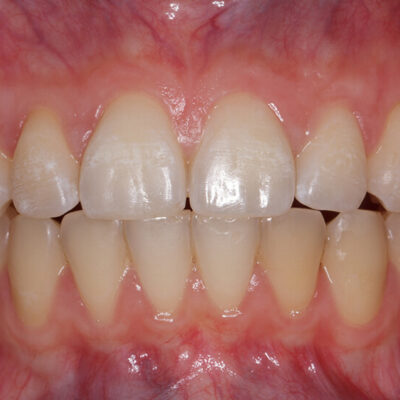

Canino superiore con recessione: prima e dopo Intervento di Chirurgia Mucogengivale con sostituti dermici

Quando le recessioni sono iniziali è sufficiente modificare le tecniche di spazzolamento e tenere le lesioni sotto controllo.

Quando iniziano a diventare un problema estetico, soprattutto nei denti anteriori , quando il paziente accusa molta sensibilità o i denti tendono a cariarsi sulla porzione di radice scoperta la Chirurgia Mucogengivale è in grado di riportare le gengive a dei livelli corretti.

La tecnica chirurgica prevede spesso il prelievo di una porzione di mucosa prelevata dal palato che andrà inserita nella zona della recessione gengivali. Questo normalmente causa un notevole fastidio al paziente nella zona di prelievo dal palato.

Da più di 15 anni la ricerca sui biomateriali ha messo a disposizione degli ottimi sostituti connettivali che evitano il prelievo di connettivo dal palato.

Per il trattamento chirurgico di circa 1.500 recessioni gengivali il dr. Patarino Domenico ha sempre utilizzato i biomateriali sostituti dermici, evitando il prelievo dal palato, con ottimi risultati clinici, evitando le complicanze possibili di questo intervento e diminuendo di molto il dolore e il gonfiore post-operatorio dei suoi pazienti.